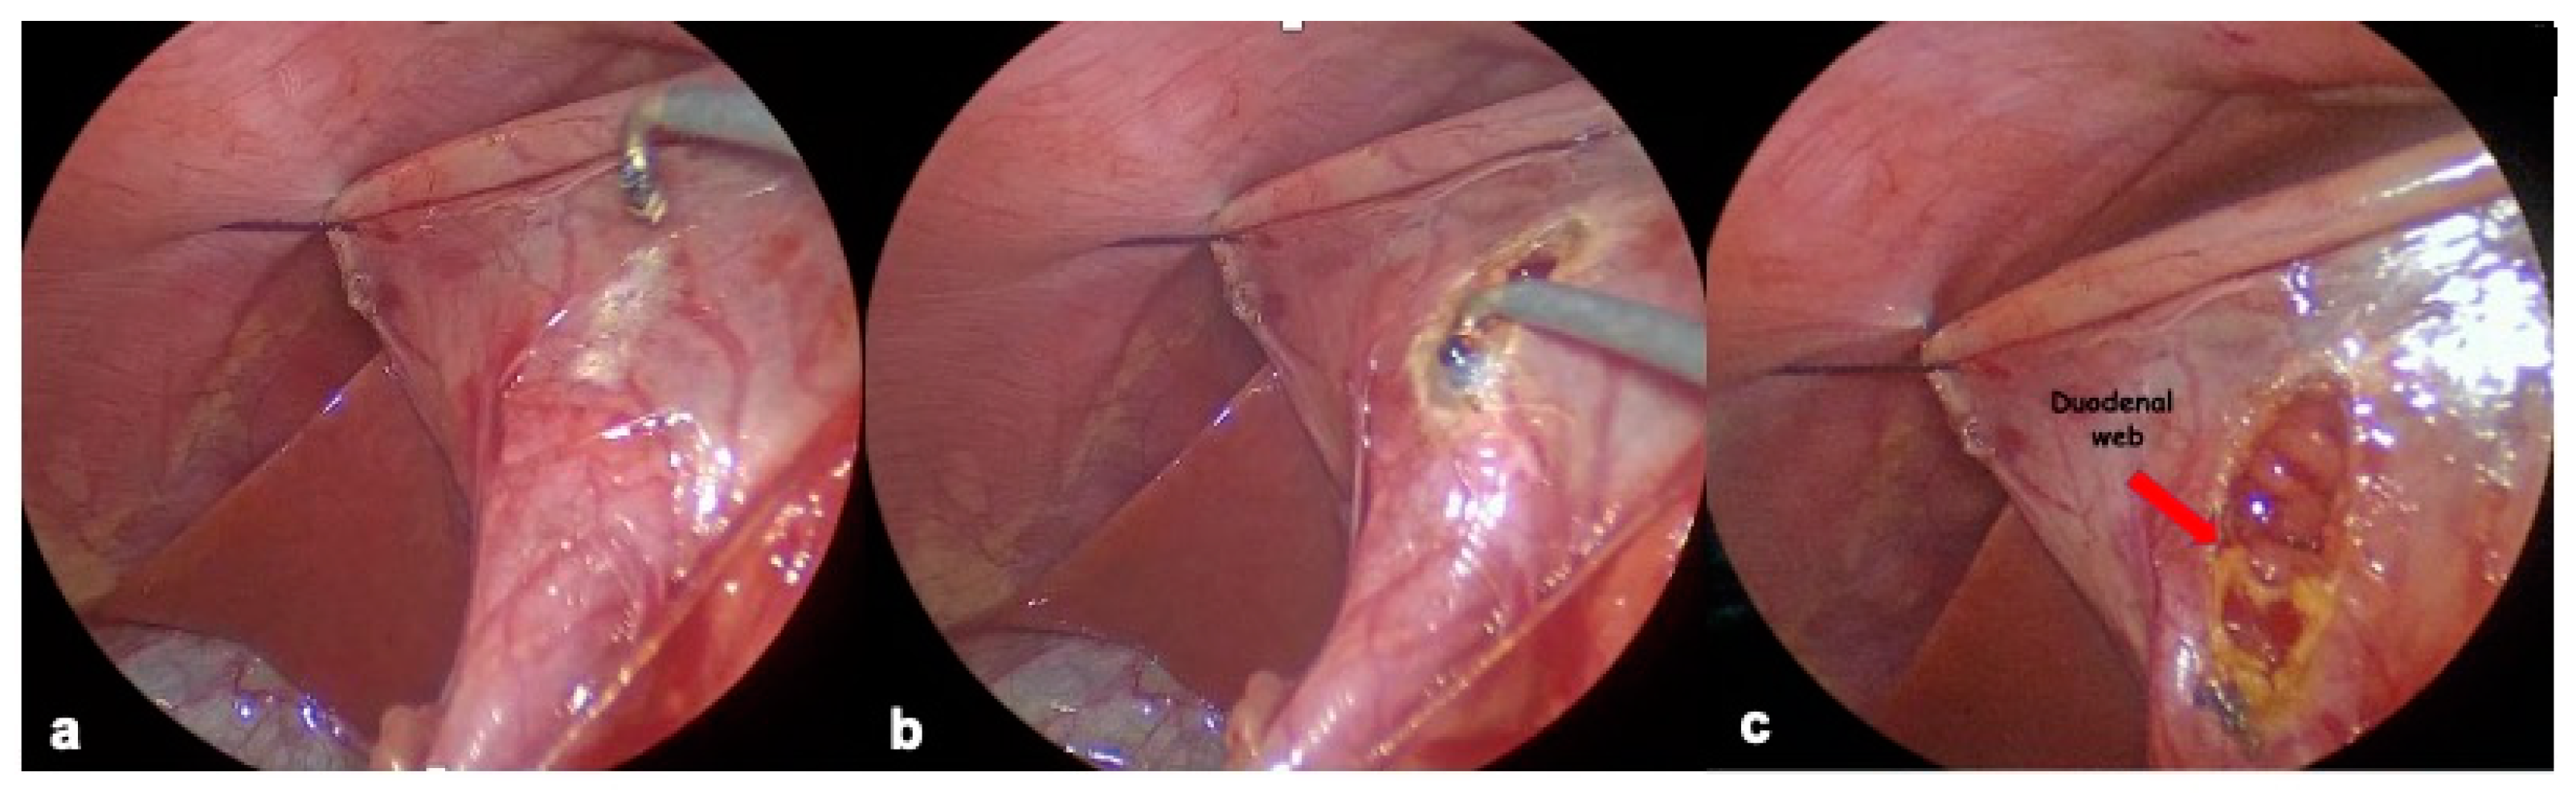

2.4.1. Endoscopic Resection

2.4.3. Duodenal Web Localization